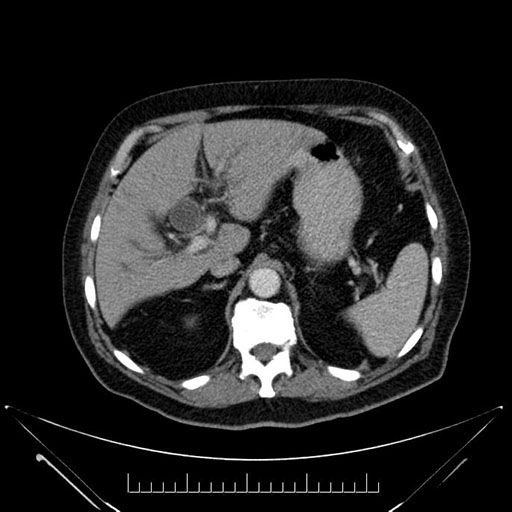

Axial - stented